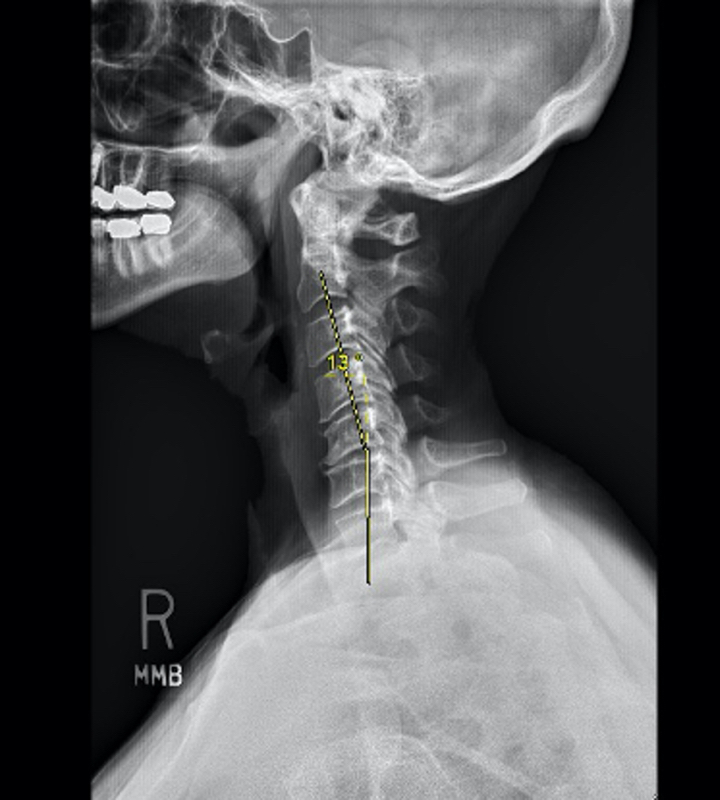

Her MRI did show disc herniations and bone spurs resulting in spinal canal stenosis. Her spinal cord was compressed, and on physical exam, she showed signs of a myelopathy. However, her cervical xrays showed a reversal of normal cervical stenosis and development of kyphosis. Given the mechanical degeneration in her cervical spine, a multilevel anterior fusion was recommended.